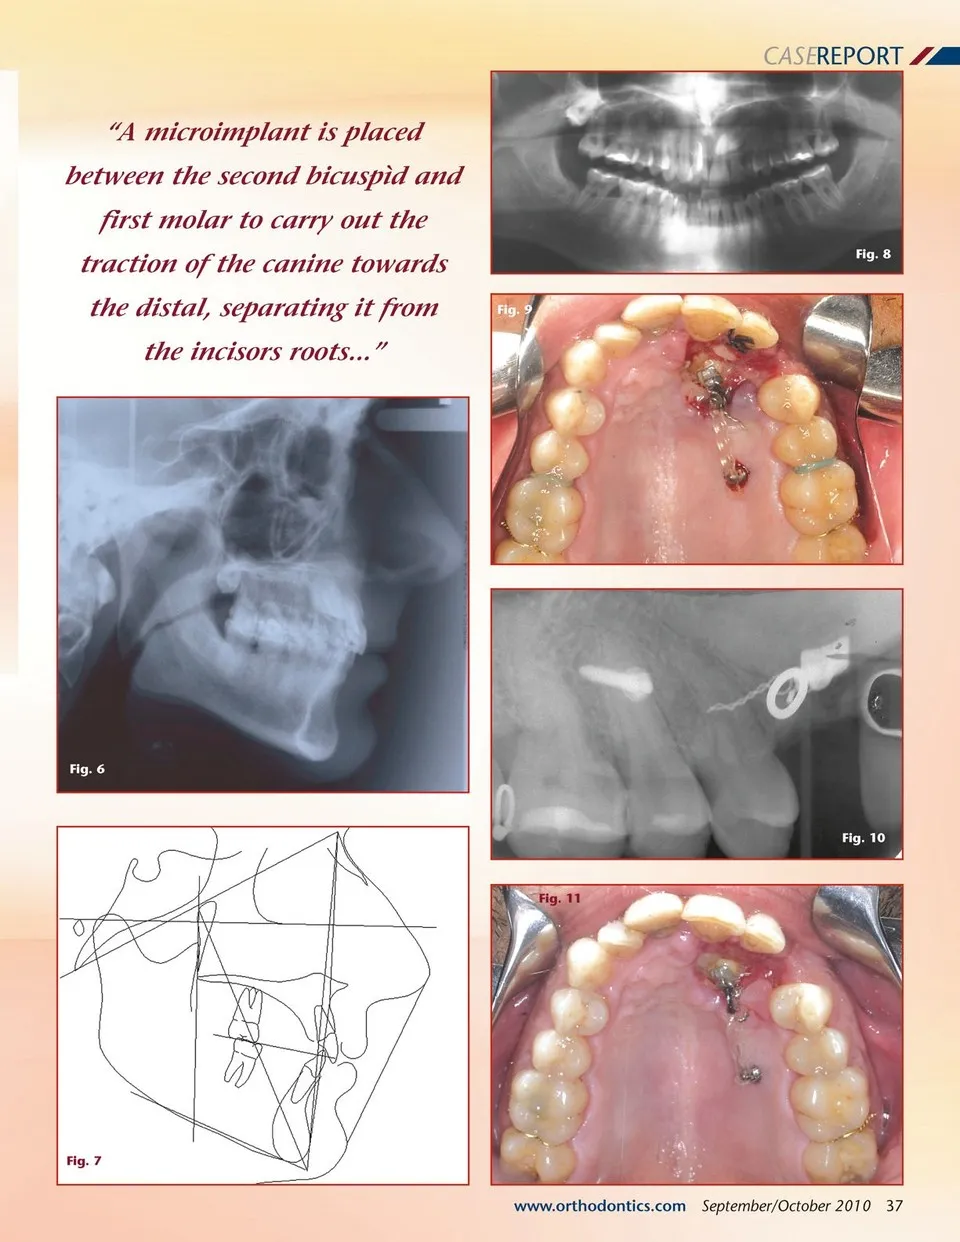

CASEREPORT Treatment of Impacted Canines Using By Pablo Echarri, DDS Microimplants Traction of impacted canines using the traditional orthodontic mechanics can provoke numerous side effects over teeth used as anchorage. To avoid this type of Figs. 1-5 undesired effect, the use of microimplants is indicated for retained canines traction. The author’s technique for microimplant usage, SARDAC (Skeletal Anchorage, Right direction, and Absolute Control) and the author’s CSW (Custom-made Straight Wire) technique are used to correct impacted canines. A 37 year old patient presented with a Class I molar malocclusion with crowding, mild rota-tions, an anterior deep bite and palatal impaction of the upper left canine. The cephalometric tracing shows a skeletal Class I malocclu-sion with mandibular retrognatia. The panoramic X-ray shows the canine in an unfavorable position due to its cusp touching the midline, and the canine’s axis angle is almost perpendicular to the incisors axis (Figs. 1 to 8). The diagnosis should be completed by a tomo-graphic study in order to determine the exact position of the canine and its relation to the roots of neighbor-ing teeth. 36 September/October 2010 JAOS Before bonding the teeth, a surgical exposure of the canine is carried out, the primary canine is extracted, and an eyelet is bonded to the impacted tooth. A microimplant is placed between the second bicuspìd and first molar to carry out the traction of the canine towards the distal, separating it from the incisors roots (Figs. 9-11). The traction is carried out using elastic chain. After having checked the effective movement of the canine, the maxillary teeth are bonded using ceramic .18” Roth prescription brackets, and a transpalatal bar with bands on the first molars and .016” NiTi archwire is also placed. The objective of this stage is to align, level and